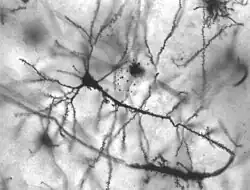

Un trouble neurologique est un trouble du système nerveux du corps humain. Les anomalies structurelles, biochimiques ou électriques du cerveau, de la moelle épinière ou des nerfs peuvent mener ou être causées par des symptômes tels qu'une paralysie, faiblesse musculaire, faible coordination, perte de sensation, des convulsions, confusion, douleurs...